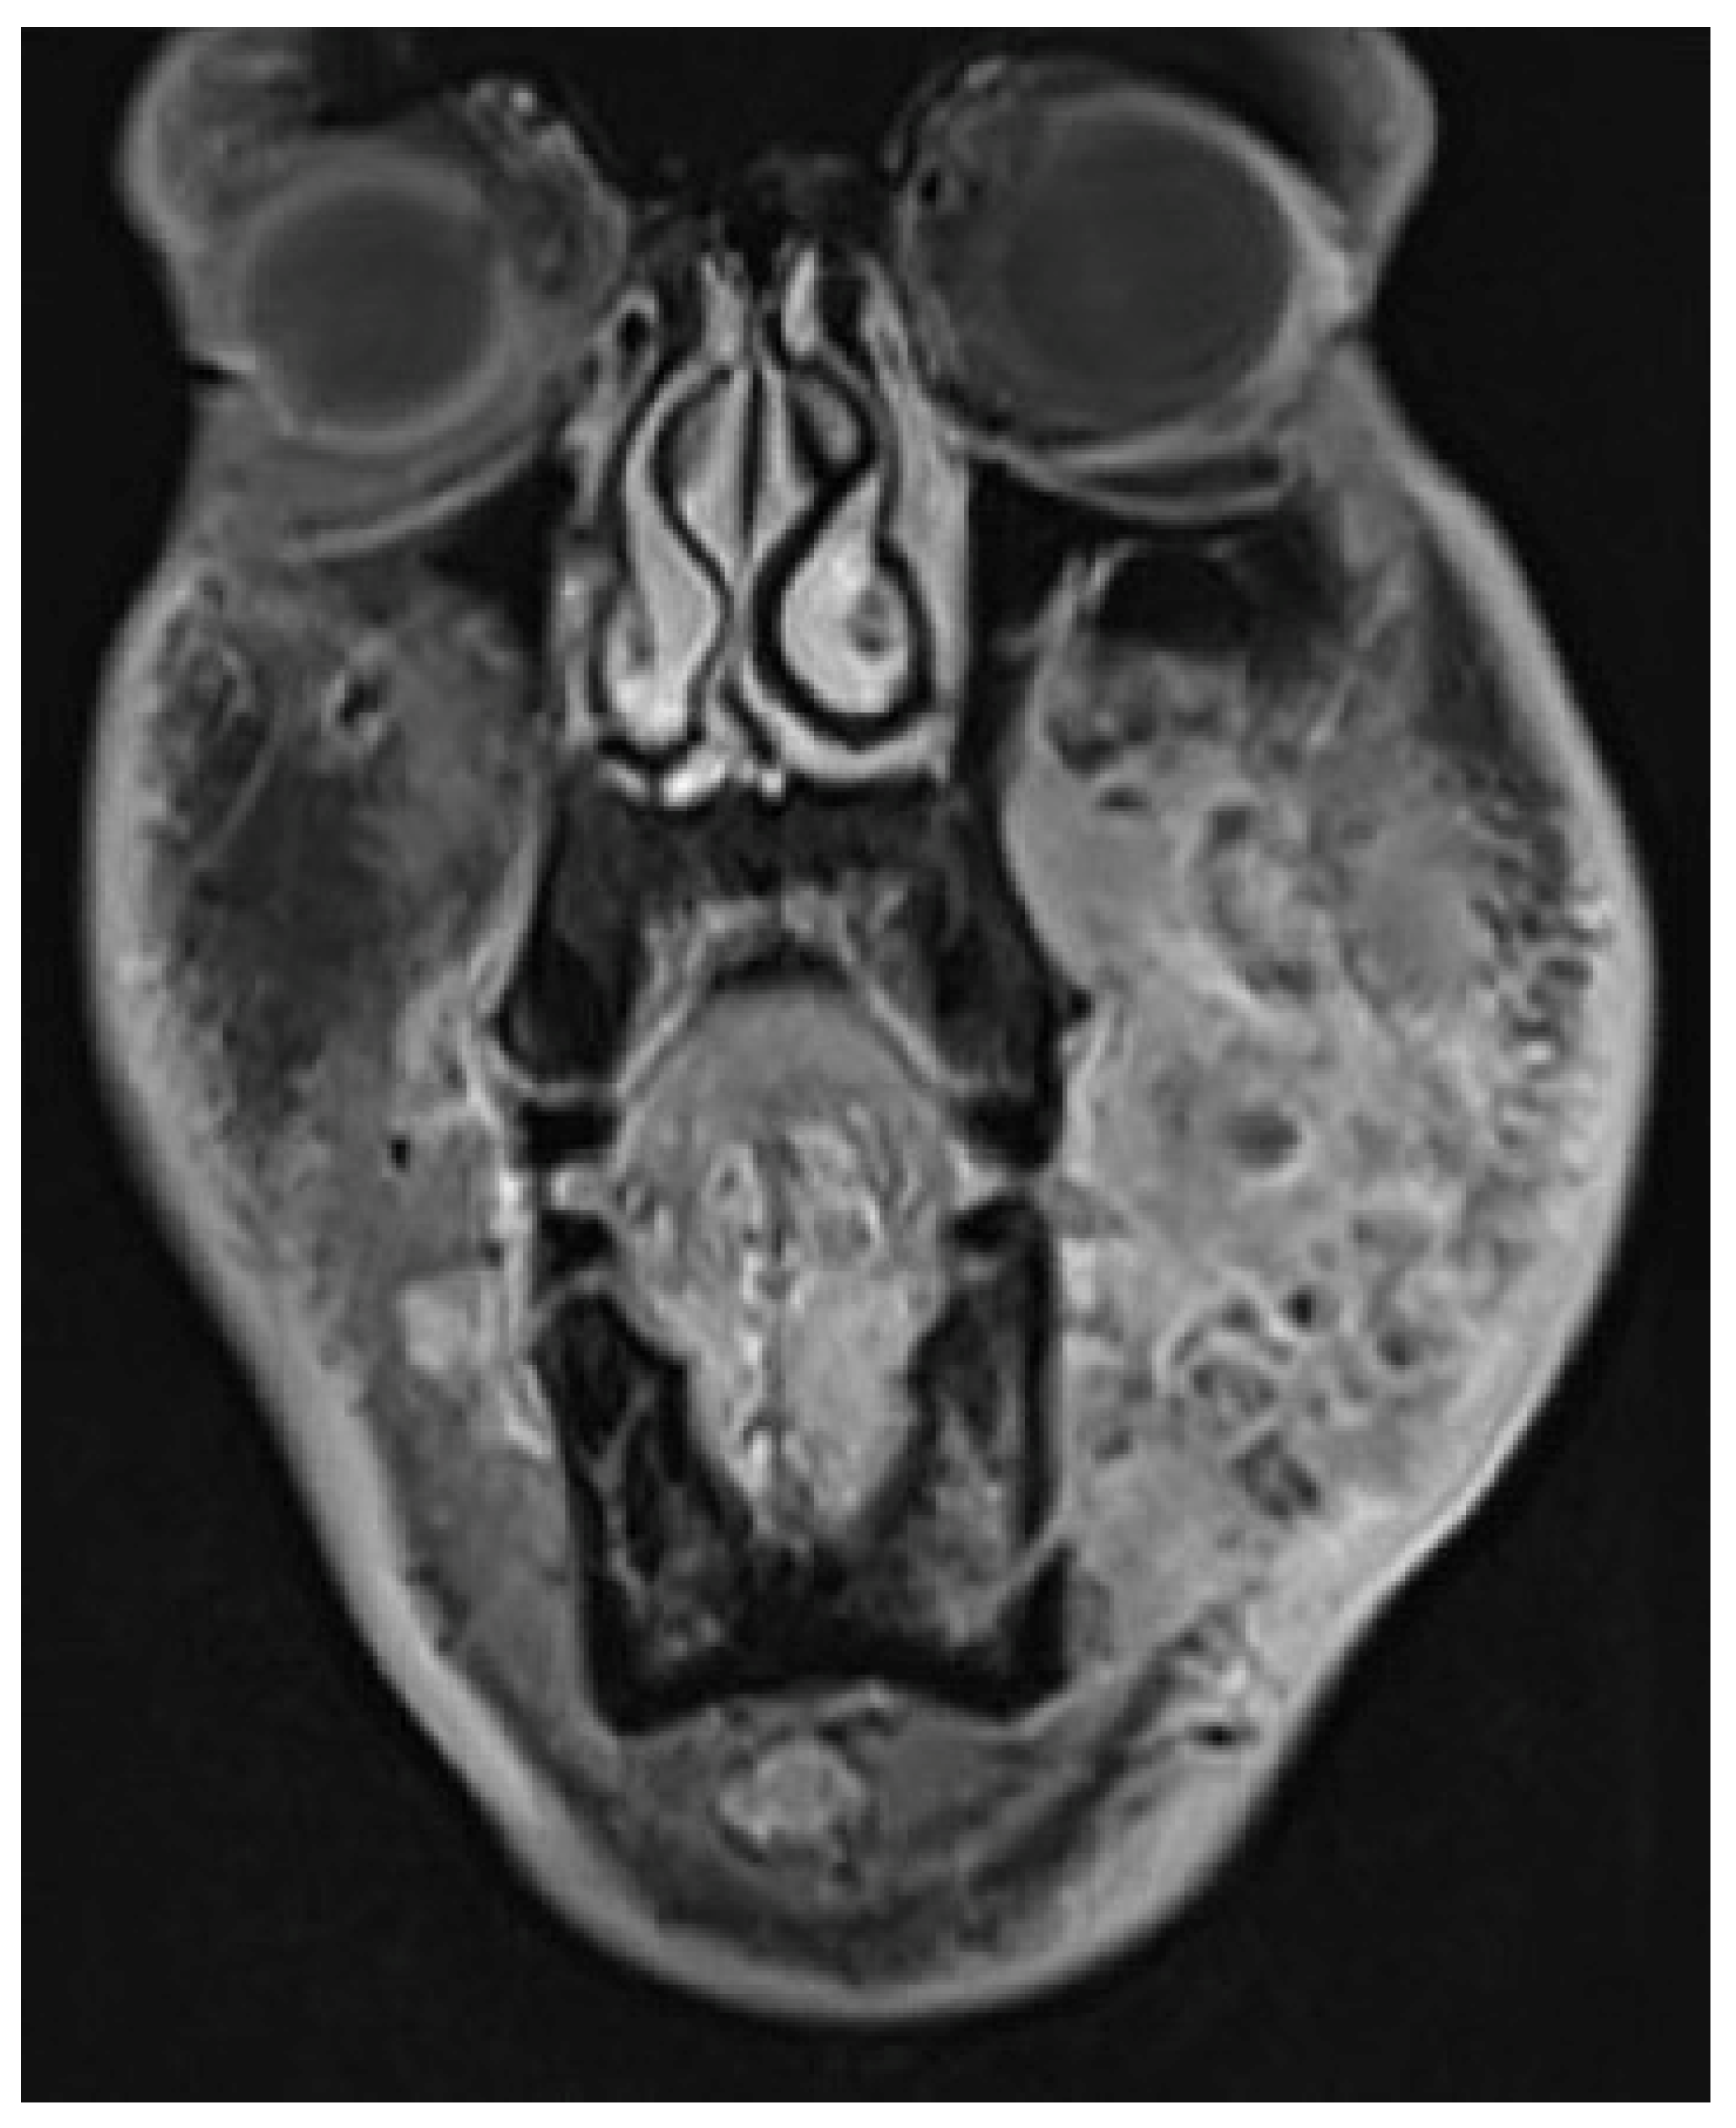

3.5. Case 5

A 36-year-old male with locoregionally advanced pT4aN2cM0 PDL-1 positive bucco-cervical/mandibular well-differentiated keratinizing squamous cell carcinoma underwent composite resection involving mandible, cheek and cervical skin in December 2024. Dual free flap reconstruction was achieved using free fibula osseomyocutaneous as well as anterolateral thigh perforator flaps. Microsurgery was completed using both Mitaka Hawksight exoscope as well as Zeiss Pentero (Carl Zeiss Meditech AG, Oberkochen, Germany) operating microscope (Figure 15, Figure 16, Figure 17, Figure 18 and Figure 19).

Figure 16. Case 5—Preoperative staging T2W magnetic resonance imaging (coronal view).